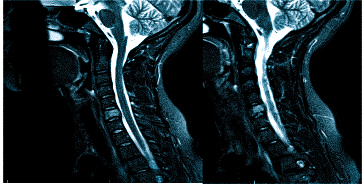

Врач определяет не только вид обследования, но и его объем. Иногда требуется дать оценку не только структурам мозга, но и воротниковой зоны: голова может кружиться и болеть при шейном остеохондрозе, грыже, воспалении нерва и пр.

Боль при шейном остеохондрозе изначально возникает в затылке, а по мере прогрессирования патологии распространяется на лобно-височную область головы

Болевой синдром при различных патологиях имеет разную интенсивность, локализацию, длительность и может сопровождаться рядом других неприятных симптомов: тошнотой, выпадением полей зрения, потерей сознания и пр. Цефалгия развивается самостоятельно или сопутствует какому-либо состоянию. Специалисты едины во мнении: если регулярно беспокоит ноющая, мигренеподобная, распирающая и другая головная боль в темечке, затылке, висках, следует обратиться на очную консультацию и пройти первичную диагностику: